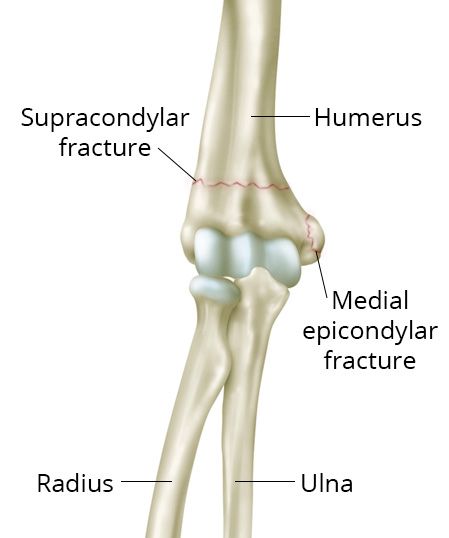

Types of elbow fractures

Common childhood elbow fractures include supracondylar fractures and medial epicondylar fractures.

Reproduced and adapted from J Bernstein, ed: Musculoskeletal Medicine. Rosemont, IL, American Academy of Orthopaedic Surgeons, 2003.